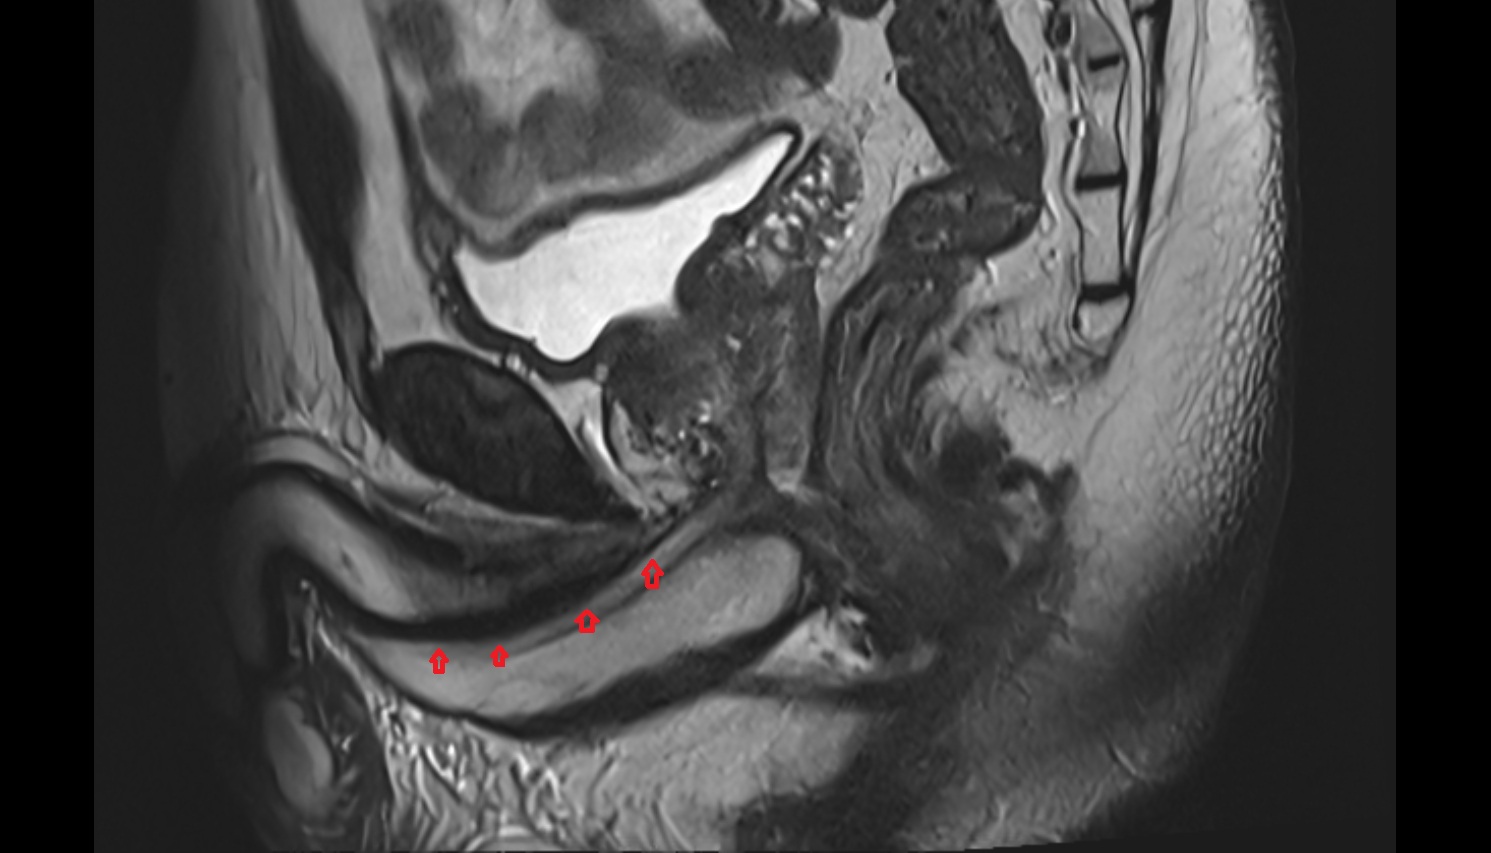

- Uterus

- Body of uterus

- Fundus of uterus

- Cervix of uterus

- Isthmus of uterus

- Vagina

- Endometrium of uterus

- Myometrium of uterus

- Junctional zone of uterus